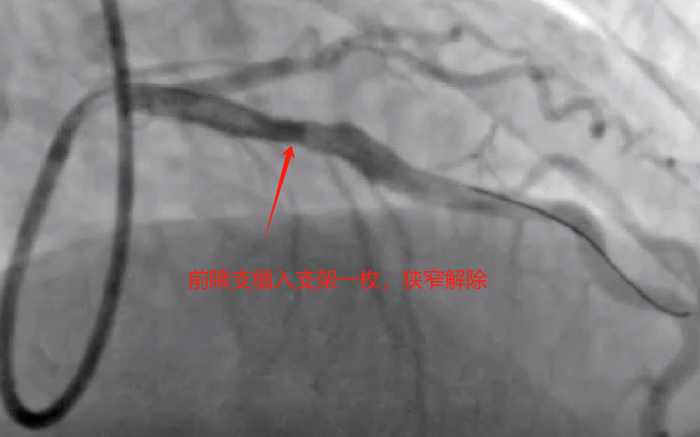

周一下午,再次为老陈进行第二次冠脉介入治疗,术中快速处理左冠前降支及回旋支重度狭窄病变,并植入支架两枚,同期简单处理右冠后三叉至后降支重度狭窄病变,一枚药物球囊处理,中段远段狭窄均无影响,完美结束手术。手术总用时1小时,造影剂用量100ml,手术很顺利,比预想的效果要好,已经超预期完成。